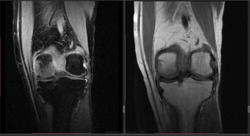

Мужчина 1963 г.р. Жалуется на боль в левом коленном суставе около 6 мес, в последний месяц стало совсем тяжко. Со слов заболел зимой, когда во время прогулки коленки сильно замерзли. Сам думаю на асептический некроз, но смущает множественность поражения.

Дмитрий, я в заболеваниях суставов не дока, но трабекулярный отек вкупе с выпотом может быть обусловлен воспалительными изменениями , но полностью начальные проявления аваскулярного некроза не могу отрицать.

я бы не поставил аваскулярный некроз. если исключена травма, дифференцировать с артритом.

Хрящ не поврежден, для артрита...